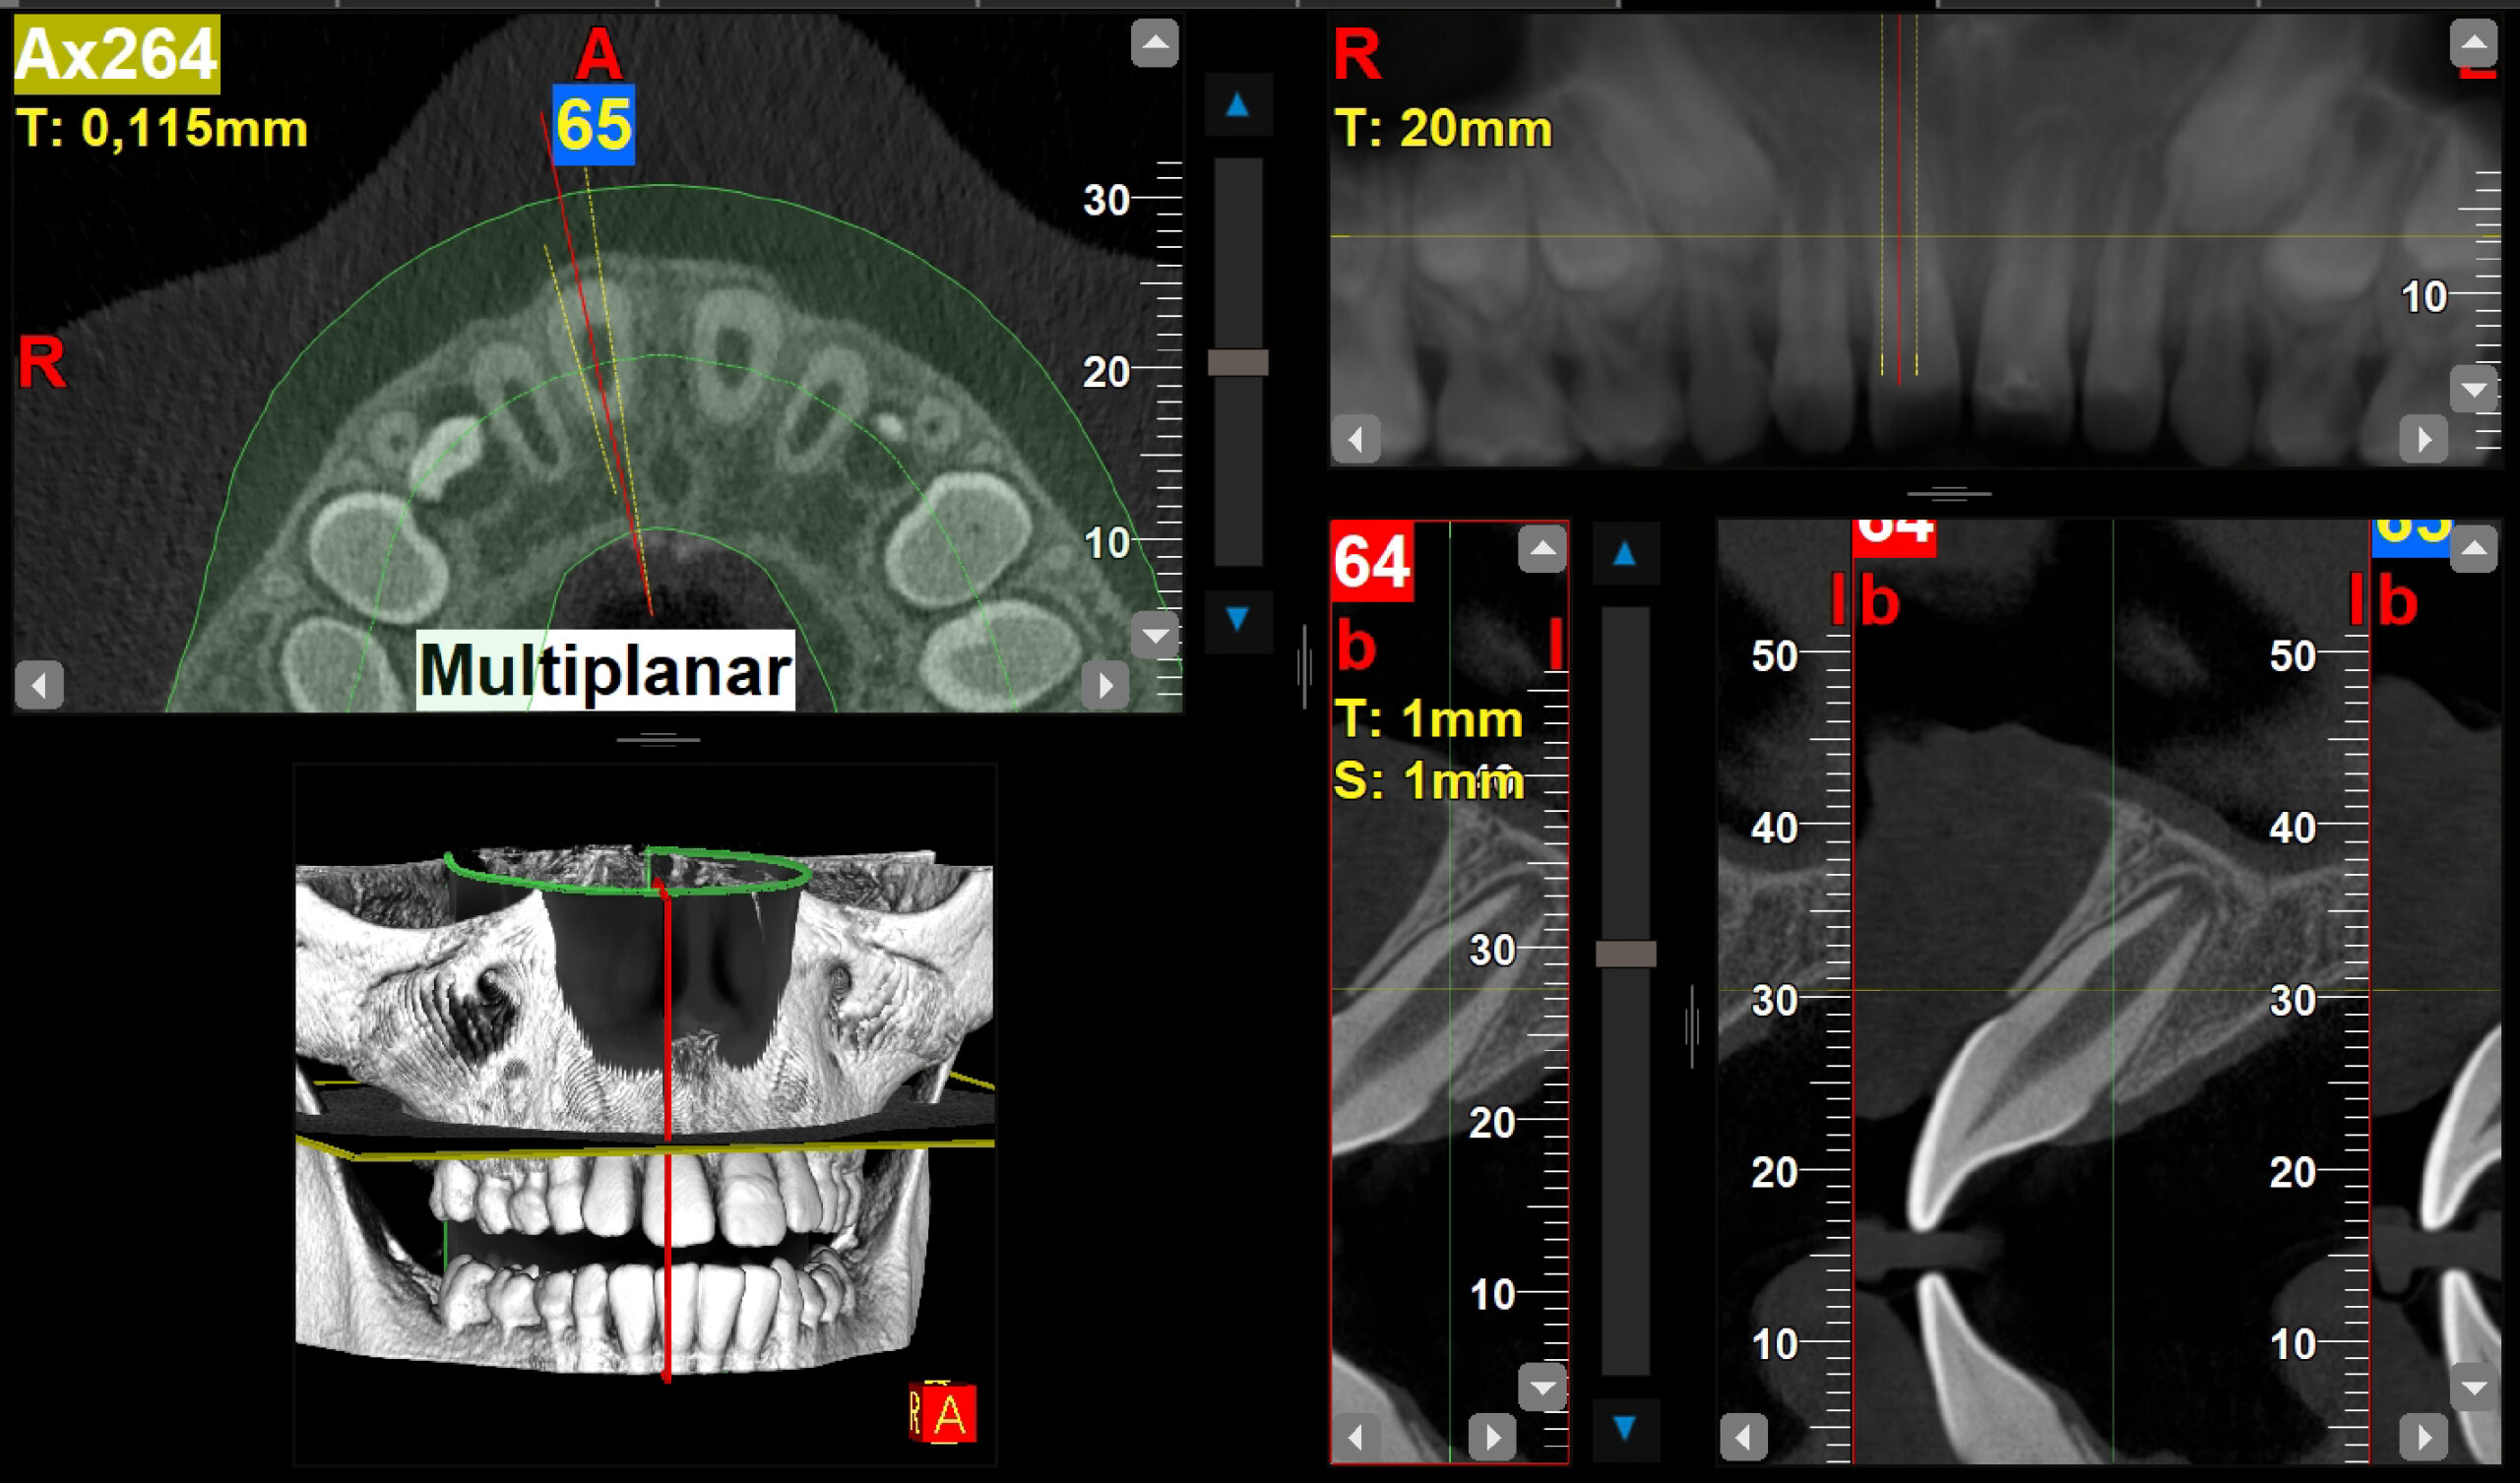

2.1 fractura coronal

Radiografías